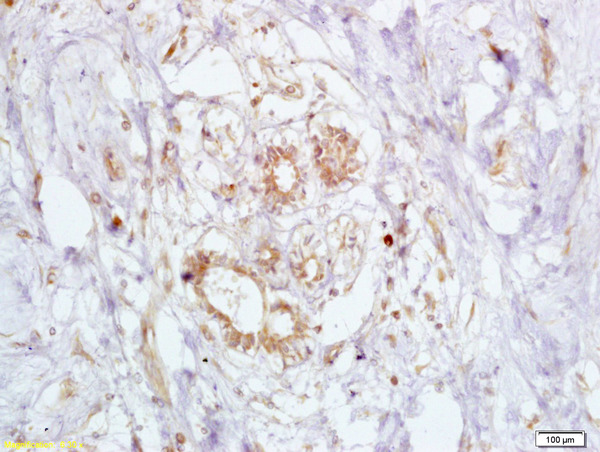

IHC-P analysis of human breast cancer tissue using GTX51235 BRCA2 antibody.

Dilution : 1:200